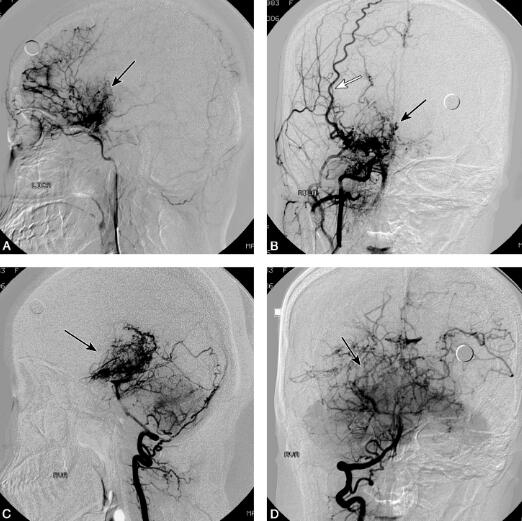

全脑DSA:双侧颈内动脉入颅段狭窄,颈内动脉远端闭塞,大量新生血管呈烟雾状增生,基底动脉尖及双侧大脑后动脉狭窄并见烟雾状血管增生(图2)。

图2 全脑DSA示左侧颈内动脉C2段狭窄远端烟雾样血管增生(黑箭头)(A);右侧颈内动脉C2段狭窄远端烟雾样血管增生(黑箭头),颈外动脉代偿向大脑前动脉供血(白箭头)(B);基底动脉尖大脑后动脉狭窄远端烟雾样血管增生(黑箭头)(C、D)

本例患者以上呼吸道感染和发热为首发症状,体温升高持续2周后缓解,随后患者出现口周疱疹,伴有言语障碍、右侧肢体偏瘫。当地医院诊断为病毒性脑炎,虽然1周后患者右侧肢体无力症状明显恢复,但总体治疗效果不明显。2个月后患者逐渐出现智能减退,生活不能自理。9个月后智能严重受损,表现为反应迟钝、自笑、不认识家人。回顾患者发病全过程,我们发现患者的临床表现为急性起病,分别以偏瘫、言语障碍、视力减退为表现形式,经一段时间临床症状可以部分缓解,但总体表现为进行性加重的过程,伴有智能减退,同时抗病毒治疗无效,这些临床表现均不能用病毒性脑炎解释。发病10个月后患者再次出现双眼视物不清,呈发作性,逐渐加重出现双眼完全看不见东西,同时出现反应迟钝、自笑,不认识家人。复查颅脑MRI示右枕叶长T1、长T2信号,DWI可见高密度影,左侧颞顶枕叶长T1、长T2信号。立即行全脑血管造影检查见双侧颈内动脉C2段高度狭窄远段闭塞,大量新生血管呈烟雾状增生。双侧颈外动脉代偿向大脑前动脉供血,基底动脉系统通过皮层支及后胼周动脉向大脑前动脉及大脑中动脉区供血。基底动脉尖和大脑后动脉近段狭窄,大脑后动脉为了代偿性地参与相应缺血区的供血,其远端不断地增生、扩张,遂形成DSA所见的异常烟雾状血管增生。此例患者告诉我们病史和临床体征是神经系统疾病诊断治疗的基础,患者虽然是以上呼吸道感染和发热为首发症状,但几次发作均有血管机制的参与,每次发作后均遗留一定程度的神经系统体征,最后患者出现精神智能障碍。调整诊断思路后发现患者外侧裂、基底节区有多发细小异常血管影像,全脑血管造影检查发现颈内动脉和椎动脉系统均有异常烟雾状血管增生,符合烟雾病的诊断。